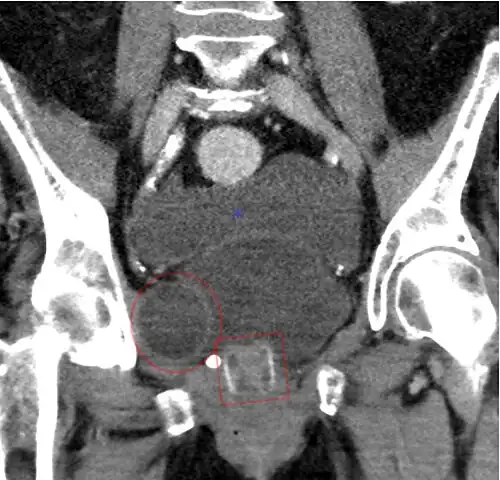

Image gallery

CT scan (coronal reconstruction) showing an AMS 800 in a woman